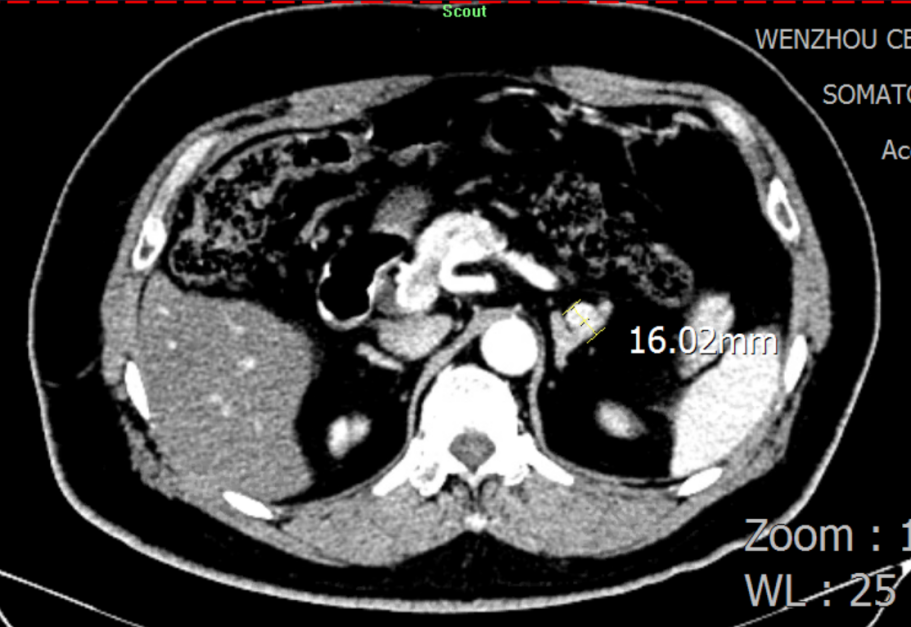

二十年前被诊断为高血压 血压控制不睬想引发两次脑出血 高峻爷的病史要从二十年前提及。2003年,在一次体检中被发明血压升高抵达150/100mmHg,经外地医院诊断为高血压,时值壮年的高先生没有太在意。 然而,让人没想到的是,2011年,在完成一次高负荷的事情后,高先生马上感应天旋地转,再度醒来时已经接受了小脑血肿扫除和去骨瓣减压术。 “幸亏救护车来得实时,我的命是脑外科医生从死神手里夺回来的。”之后,高先生提前过上了退休生涯,只管遵医嘱准时服用降压药,但血压控制并不睬想,还被诊断为重度壅闭性睡眠呼吸障碍综合征,使得血压控制更难了。 2019年,149/85mmHg的血压再次向他的血管提倡攻击,高先生因右侧小脑血肿再次入院。这对刚刚脱离手杖的高先生而言,又是一次重大攻击。 二十年后经精准诊断 行左侧肾上腺切除术后病情显著改善 心肌标记物、肝肾功效、血糖、血脂、甲状腺功效、BNP/NT-proBNP、超敏肌钙卵白、电解质……厚厚的一沓检测报告中,晚年科陈主任关注到有十几张血钾、尿钾异常报告。通过询问家族病史,陈主任相识到高峻爷的母亲和弟弟均患有高血压、低钾血症,且恒久服用氯化钾缓释片,其母亲已于十年前因脑出血去世。 陈主任决议将高峻爷以高血压伴低钾血症病因收治入院,并复查血钾,行盐皮质激素相关高血压筛查及全腹部CT扫描。 盐皮质激素相关高血压筛查(卧位 早上6点) 盐皮质激素相关高血压筛查(立位 早上8点) 检测报告出来后,陈主任第一时间请内渗透科余主任会诊。余主任看了报告,第一时间想到了最常见的引起高血压伴低钾血症的内渗透科疾病——原发性醛固酮增多症(简称“原醛症”)。 “以前,各人都以为原醛症是一个少见病,遇到高血压伴低血钾就直接给患者上螺内酯。着实原醛症有六种分型,每种都有差别的诊疗计划。若是是醛固酮瘤,高血压甚至有治愈的希望。”余主任感应很遗憾,“这个检查要是早做二十年就好了。” “从卧位变为立位,检测报告显示,患者的醛固酮水平没有像康健人群一样升高,反而下降了。因此,我们推测他是可手术治愈的原醛症-醛固酮瘤患者。”果真,CT效果进一步佐证了余主任的诊断。 肾上腺增强CT:思量左侧肾上腺结节状增生

思量到患者的家族病史,为扫除家族性的醛固酮增多症,在吴主任的建议下,患者先做了基因检测,基因检测效果并未提醒家族性醛固酮增多症。